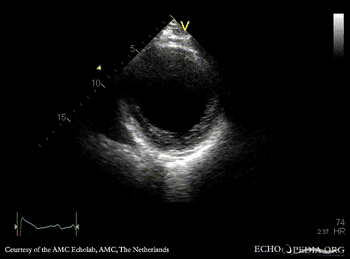

PLAX: large aneurysm of left ventricle